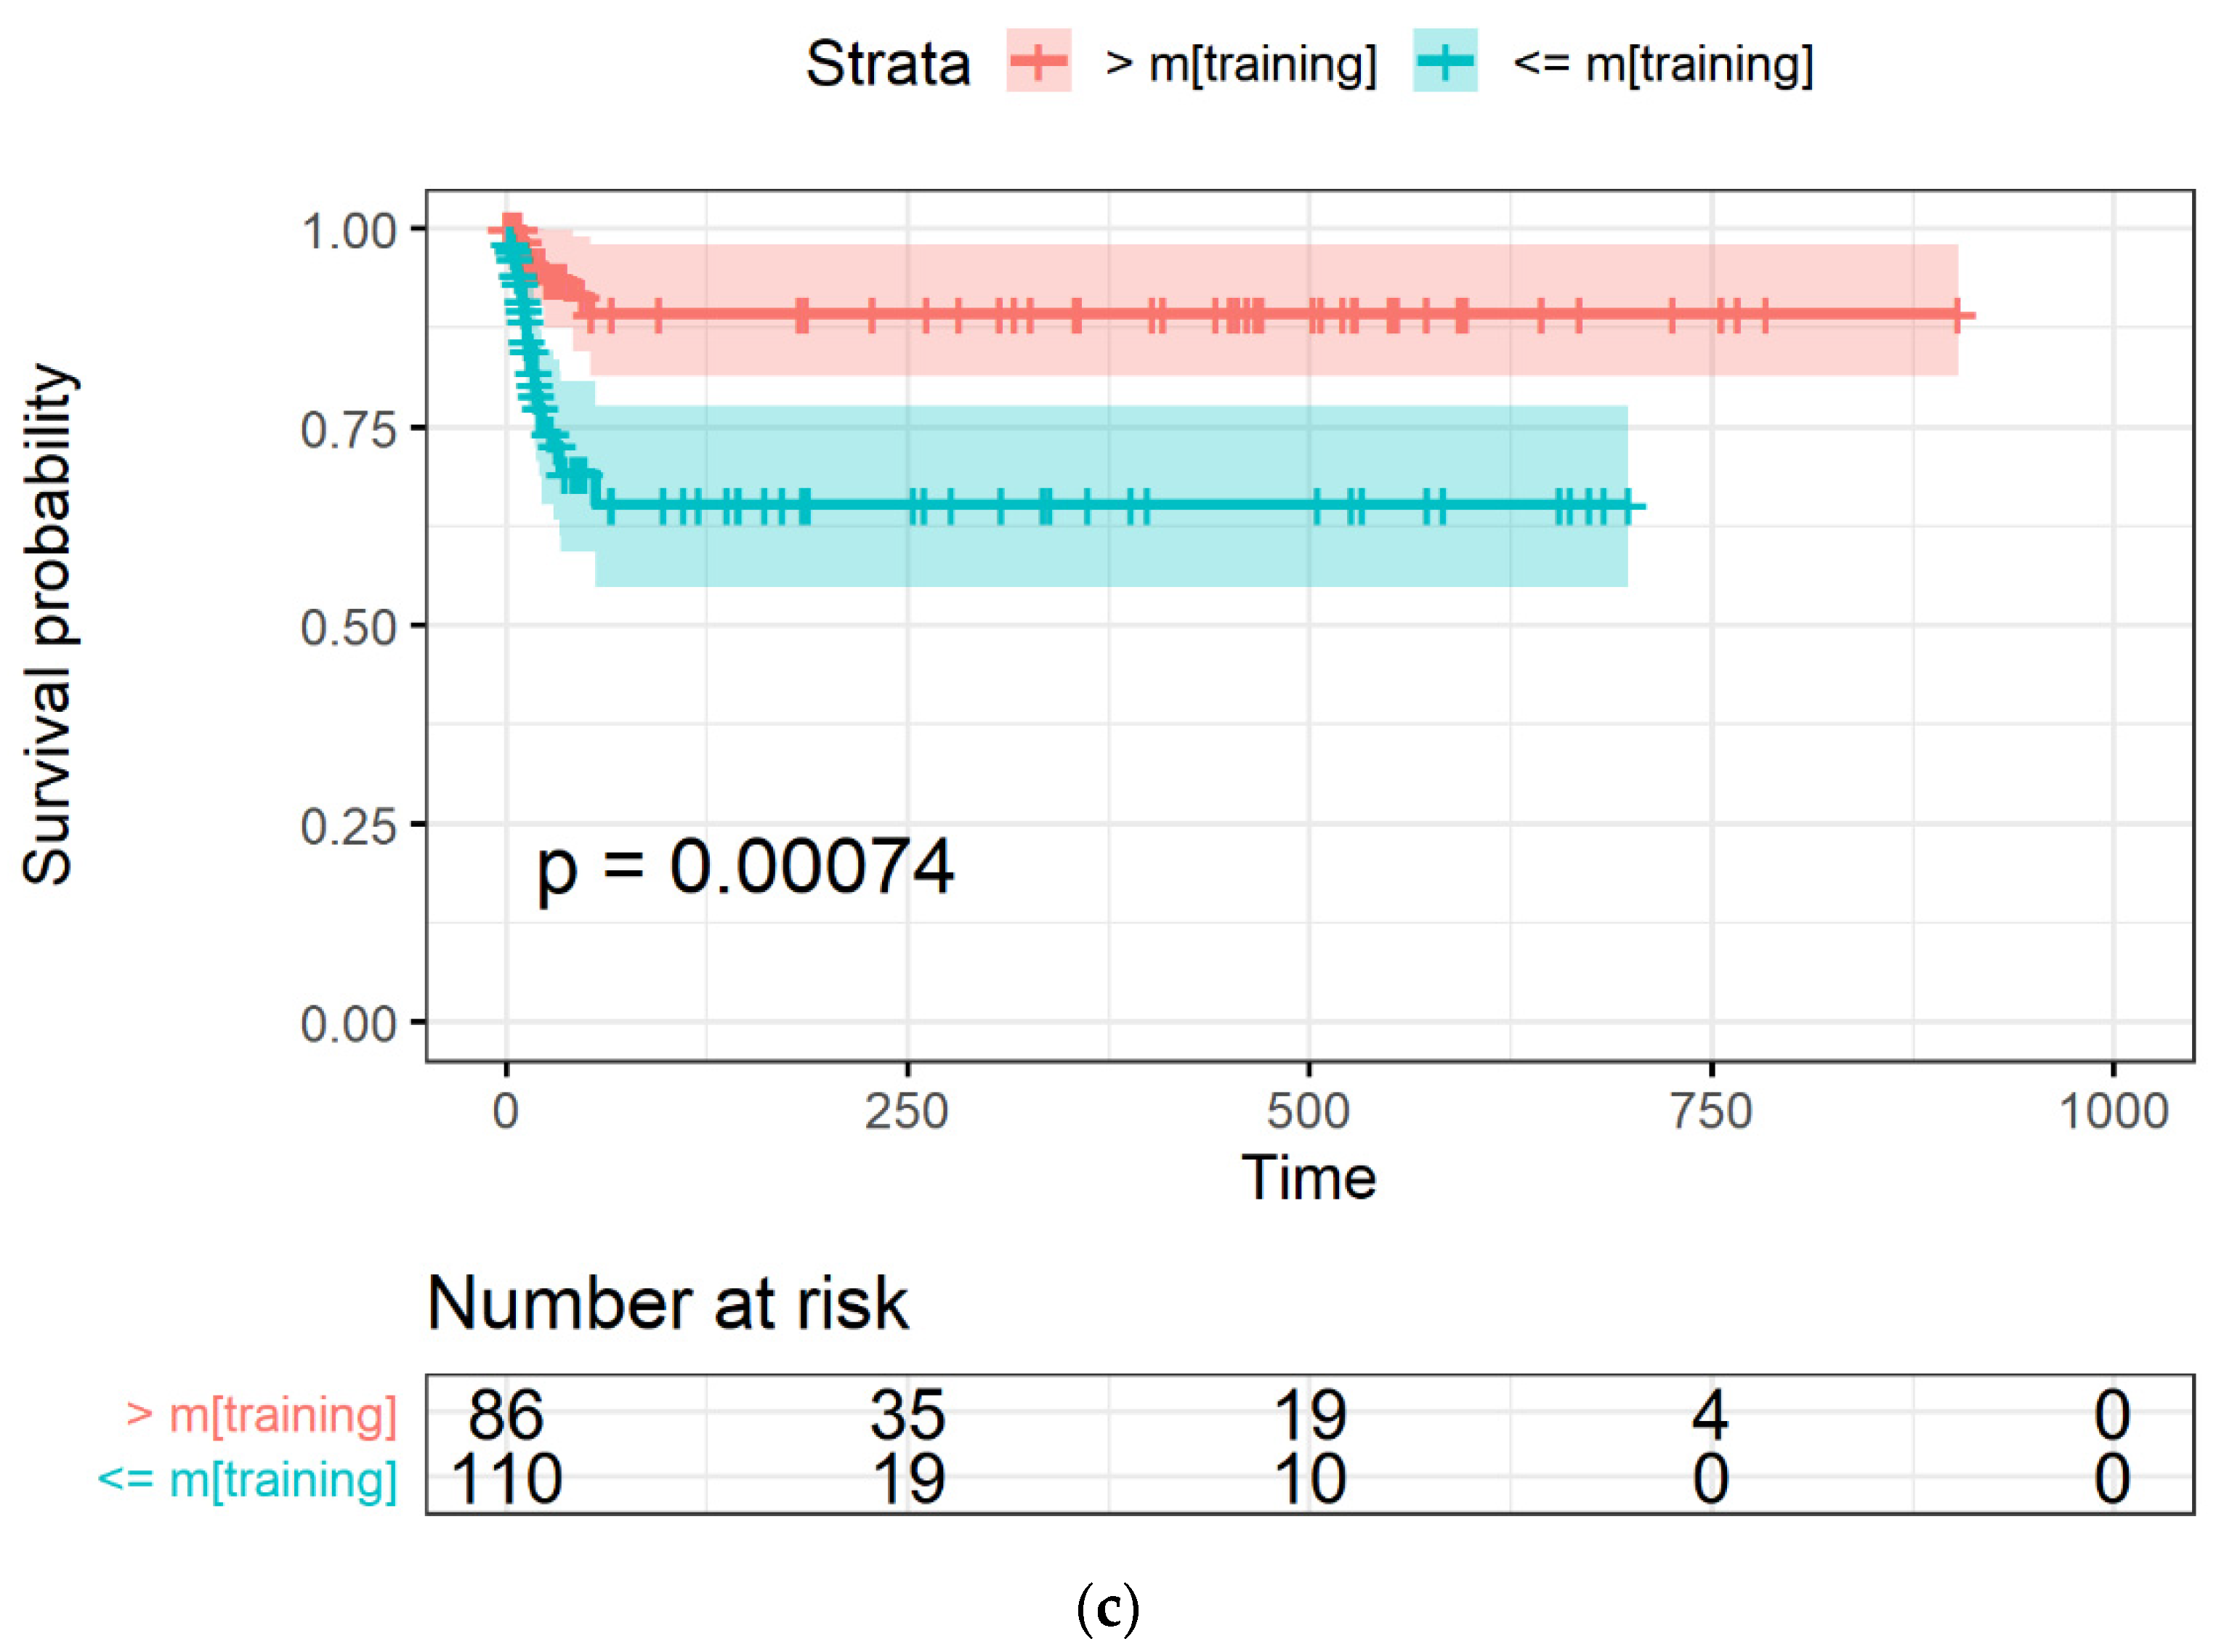

2.3.4. Model Evaluation through Survival Curves